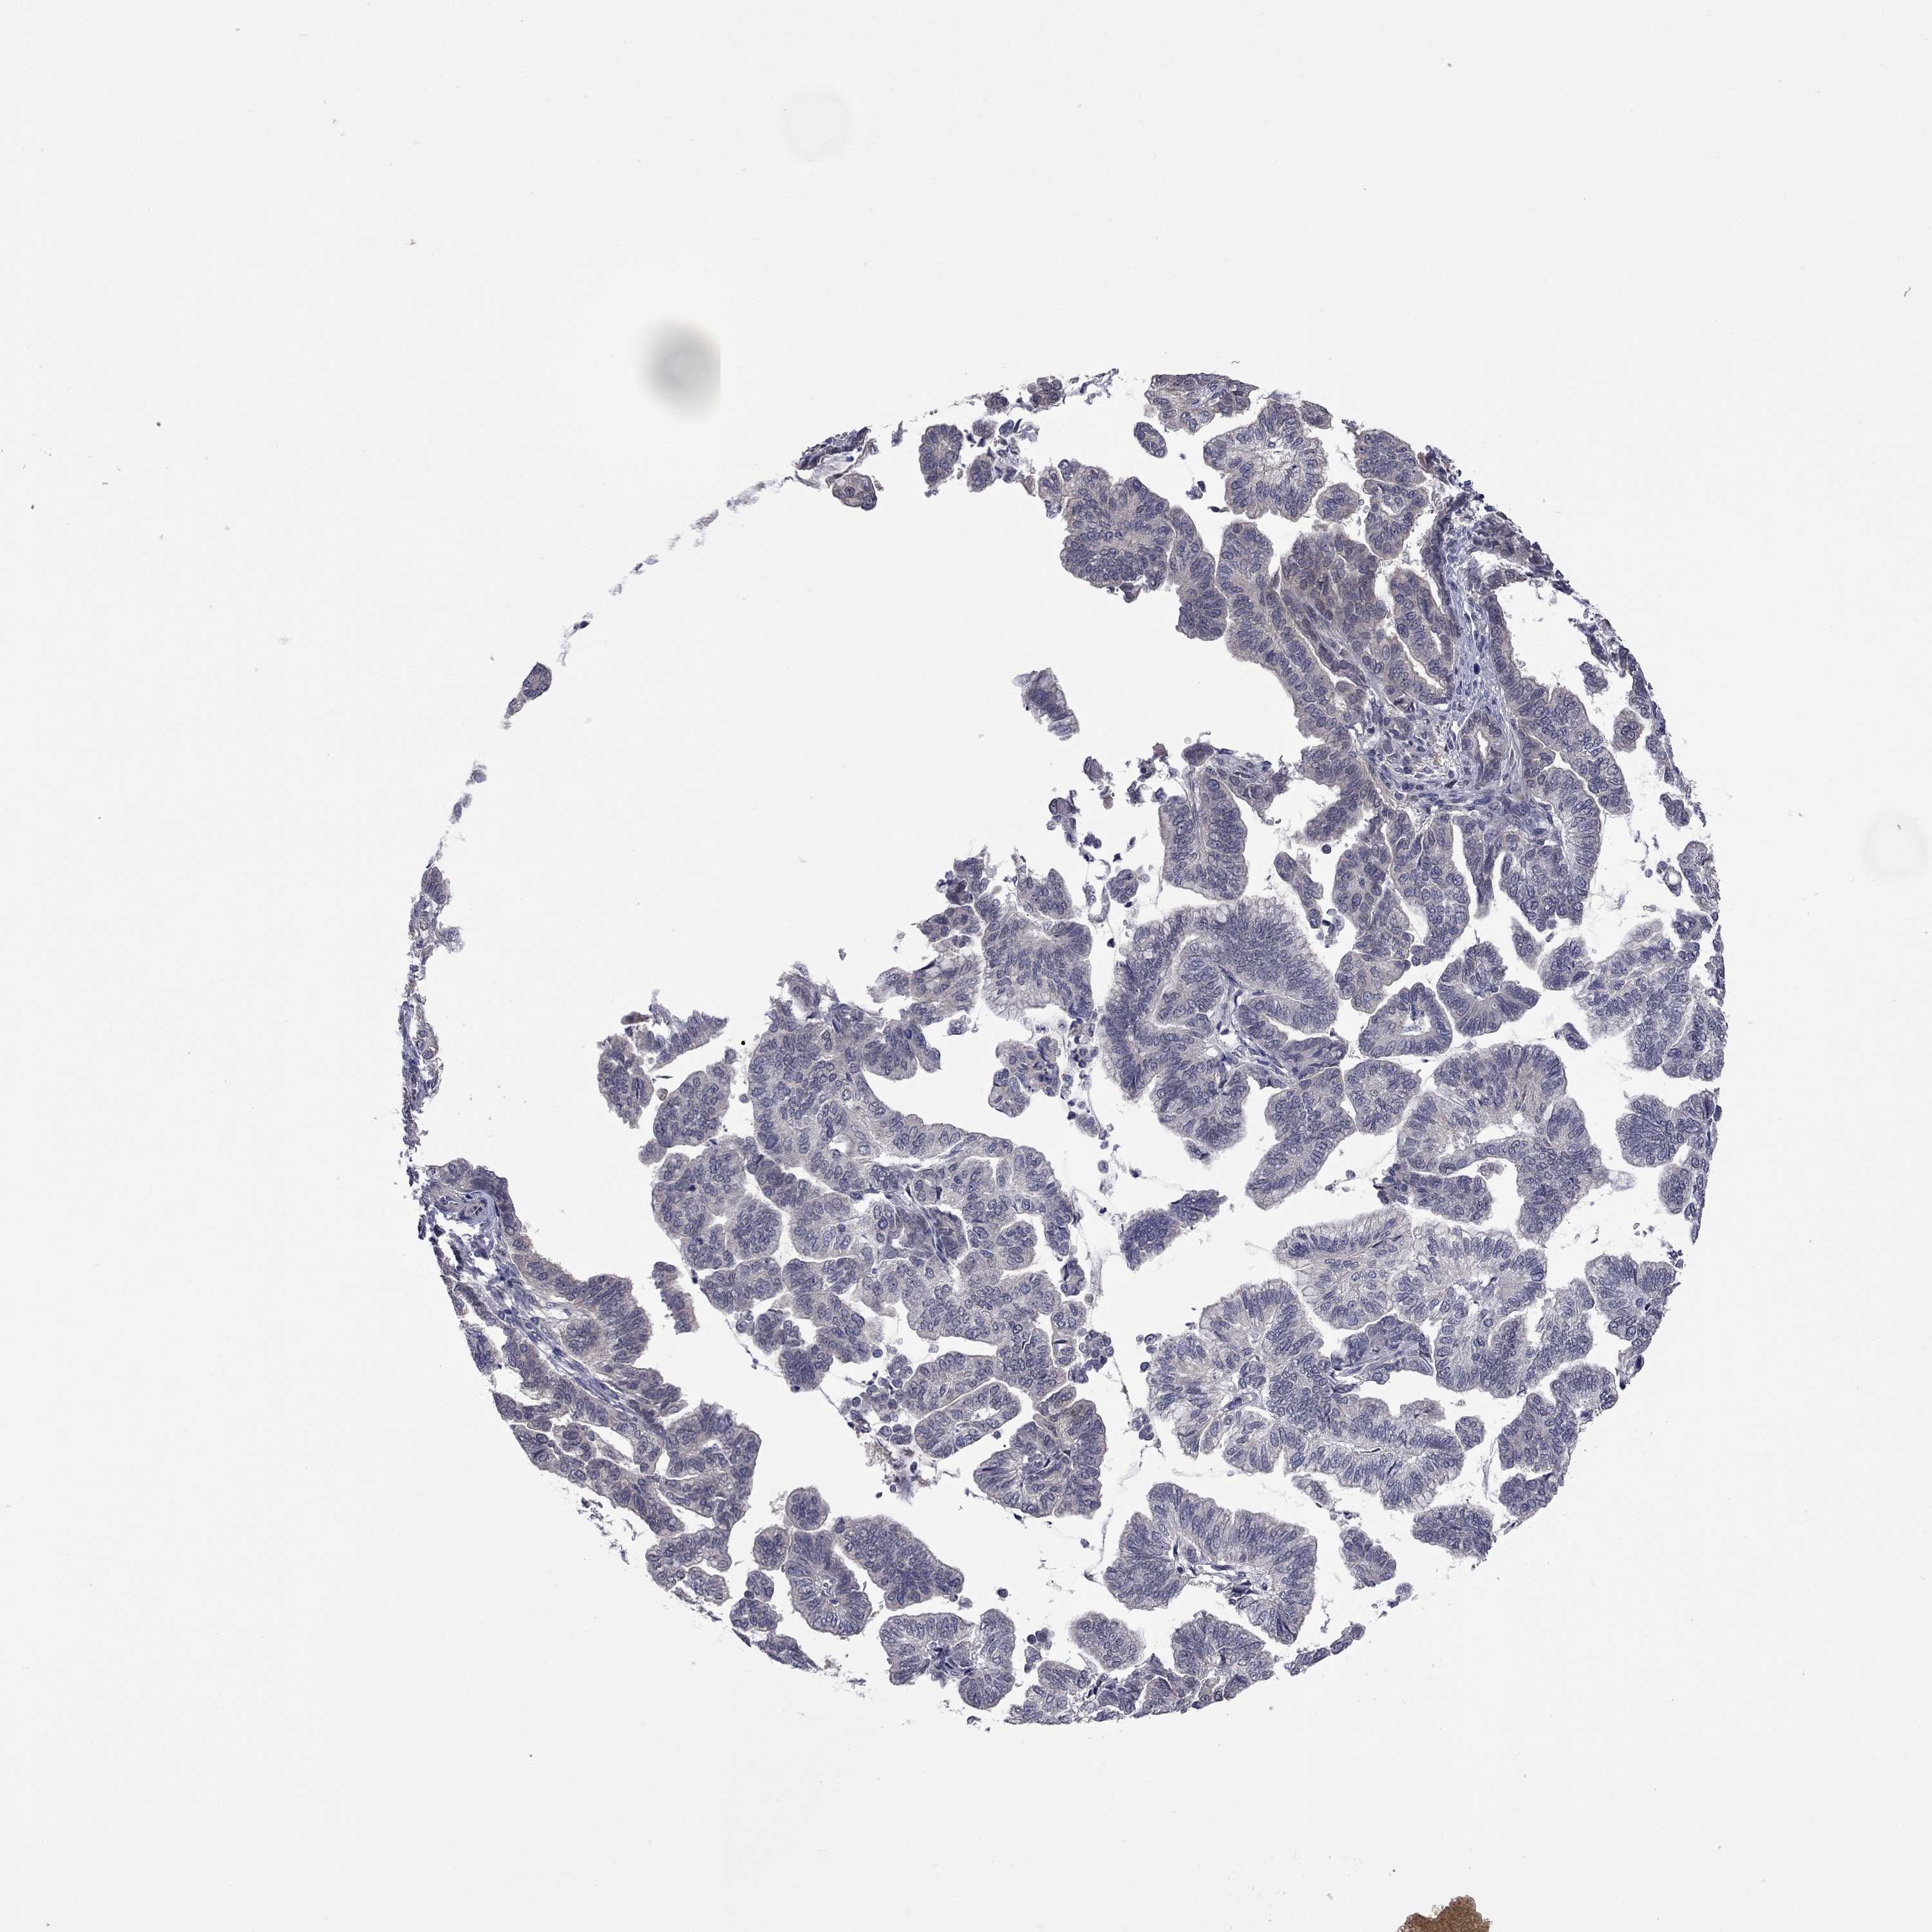

STOMACH CANCER - Protein expressioni

A mouse-over function shows sample information and annotation data. Click on an image to view it in a full screen mode. Samples can be filtered based on level of antibody staining by selecting one or several of the following categories: high, medium, low and not detected. The assay and annotation is described here.

Note that samples used for immunohistochemistry by the Human Protein Atlas do not correspond to samples in the TCGA dataset.

Antibody stainingi

Antibody staining in the annotated cell types in the current human tissue is reported as not detected, low, medium, or high, based on conventional immunohistochemistry profiling in selected tissues. This score is based on the combination of the staining intensity and fraction of stained cells.

Each image is clickable and will lead to virtual microscopy that enables deeper exploration of all samples and also displays staining intensity scores, fraction scores and subcellular localization as well as patient and tissue information for each sample.

Antibody HPA044041

Adenocarcinoma, NOS